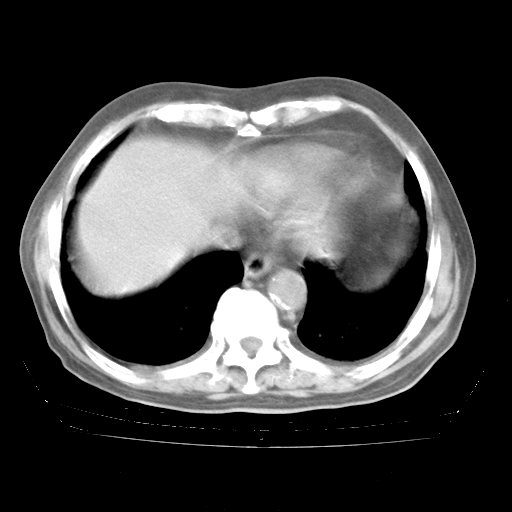

4月28日肺部CT

腹部B超:胆囊壁增厚,肝、胆、胰、脾、肾无异常,肠系膜淋巴结、腹膜后淋巴结无增大。